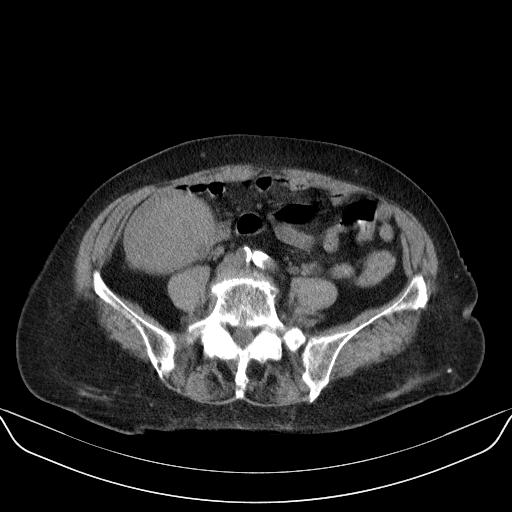

以下是引用yuhongjun在2010-3-12 6:32:00的发言:[br]回肠末端间质瘤,不除外阑尾粘液囊腺瘤,臀部注射性肉芽肿钙化. [br] [br]